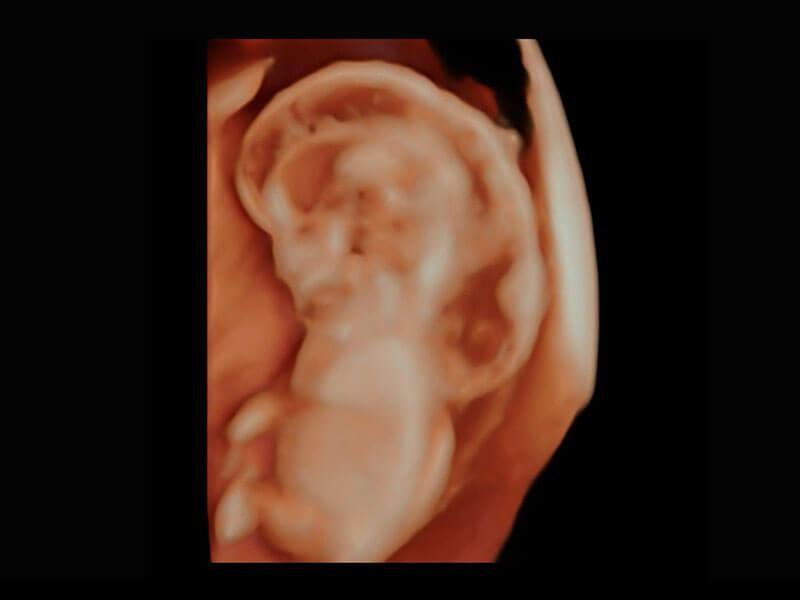

P60在胎儿早孕期超声筛查中为您带来优异的图像质量。

• 高分辨率容积成像-早孕胎儿